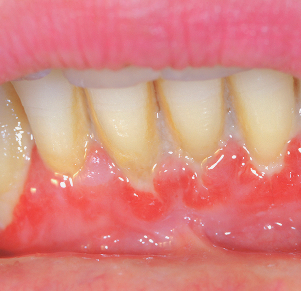

잇몸에서 피가 나거나 붓는 증상이 있는 경우

스케일링 후 주의사항

시술 후 일시적으로 시림이나 출혈이 있을 수 있습니다.

술 당일은 너무 뜨겁거나 찬 음식, 자극적인 음식은 피해주세요.

하루 정도는 부드러운 칫솔질로 가볍게 세정하는 것이 좋습니다.

정기적인 스케일링(6개월~1년 간격)을 통해 잇몸건강을 관리하세요.